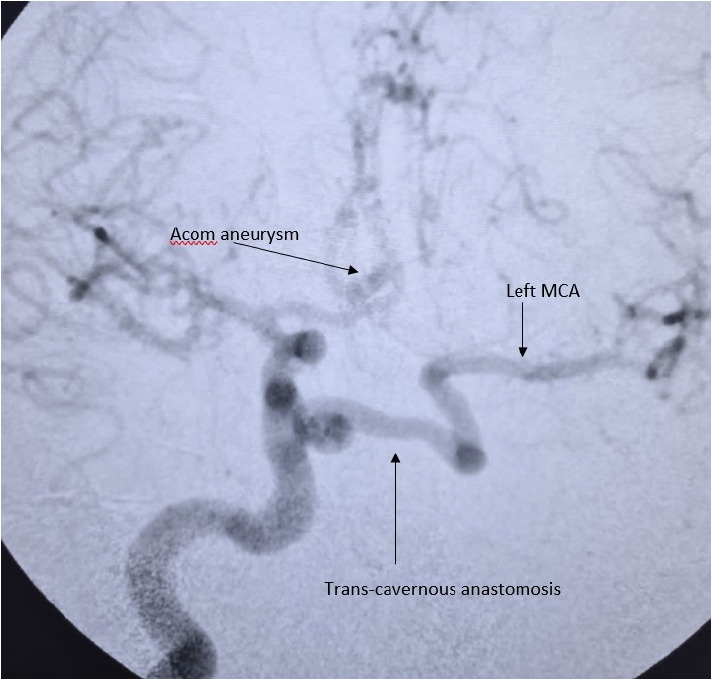

Developmental anomalies of internal carotid artery (ICA), being rare entities, are mostly asymptomatic by themselves because of good collateral supply. However, when present with other associated intracranial anomalies requiring treatment, there can be catastrophic consequences, if special attention is not paid to this condition. We present a case of 36 years old male, who reported to our emergency department with complaints of headache and loss of consciousness. He was diagnosed as a case of ruptured anterior communicating aneurysm with subarachnoid hemorrhage and agenesis of left ICA with trans-cavernous anastomosis. He underwent clipping of aneurysm and was discharged uneventfully. This report highlights the importance of skillful microsurgical clipping in extremely high-risk conditions, in contemporary era of hybrid neurosurgeons.